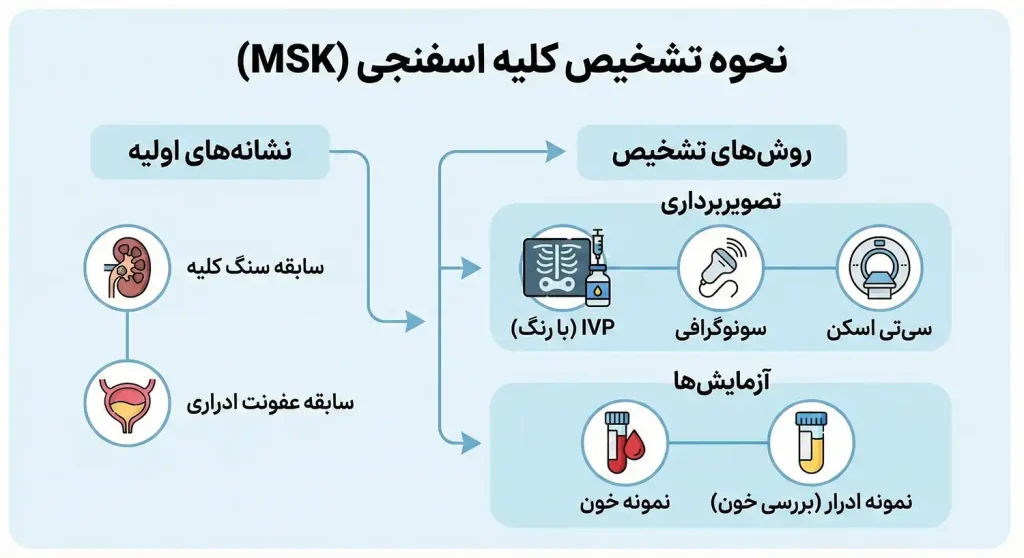

نحوه تشخیص کلیه اسفنجی

در صورت داشتن سابقه سنگ کلیه یا عفونت سیستم ادراری، پزشک از تست تصویربرداری برای کمک به تایید ابتلا به MSK استفاده می کند.

تشخیص شامل یک نوع تست اشعه ایکس به نام پیلوگرام داخل وریدی (IVP) است که اوروگرام داخل وریدی نیز نامیده می شود.

این تست از یک رنگ مخصوص استفاده می کند که برای کمک به پزشک برای مشاهده کلیه ها و هرگونه مشکل از قبیل وجود کیست در کلیه ها یا انسداد مجرای ادراری، تزریق می شود.

تست های تصویربرداری دیگر شامل فراصوت یا سی تی اسکن است.

ممکن است پزشک، نمونه گیری خون و ادرار را نیز برای بررسی نحوه فعالیت کلیه ها و وجود هرگونه علائم عفونت، انجام دهد.

پزشک، وجود خون در ادرار را نیز بررسی خواهد کرد.